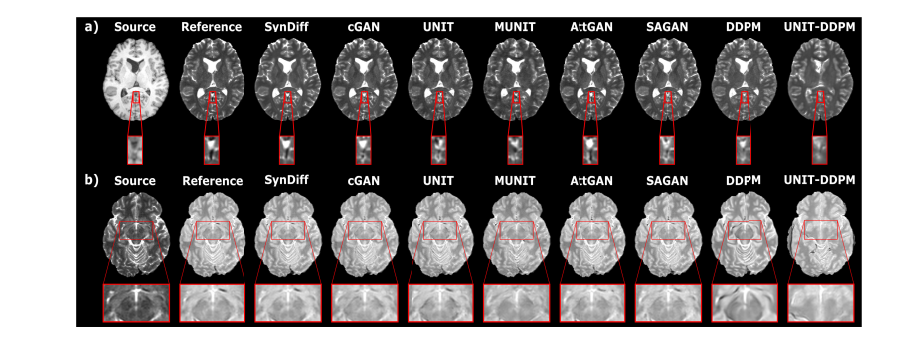

Fig. 3. SynDiff's demonstration on IXI focused on translating between MRI contrast modalities. Synthesized images generated by competing approaches are presented alongside their respective source and reference target images in representative cases such as a) T1 to T2 conversion and b) T2 to PD mapping. The display windows for cases a) [0, 0.65] and b) [0, 0.80] were selected. The performance of SynDiff surpasses that of baseline methods by demonstrating reduced noise levels and artifacts while maintaining high anatomical accuracy.

Fig. 3. 在IXI数据集上展示了SynDiff在MRI对比度之间的翻译比较。对现有方法的合成结果进行了对比分析,并分别展示出代表性的源图像(T1或T2)及其目标(参考)图像:a) T1→T2转换;b) T2→PD转换。各子图显示窗口分别为a) [0, 0.65]区间;b) [0, 0.80]区间范围。相较于基线方法,在保持较高解剖学准确性的同时,SynDiff生成的图像呈现出更低噪声水平及更少伪影干扰

Fig. 4. SynDiff在BRATS上实现了MRI对比转换的任务展示。合成图像配合来源图像与参考目标图像(ground-truth)进行展示,在a) T1到T2、b) T2到FLAIR等典型任务中可见。a)窗口范围设定为[0 0.75]、b)为[0 0.80]。与基准方法相比,SynDiff降低了噪声/ artifact水平并更精确地呈现了细节结构.

图4展示了SynDiff在MRI对比度转换中的应用效果,在BRATS数据集上进行了验证。该方法呈现了合成图像以及代表性的源图像与目标(参考)图像:a) T1到T2的转换;b) T2到FLAIR的转换。具体范围为a) [0 0.75];b) [0 0.80]。与基线方法相比,SynDiff显著降低了噪声和假影水平,并能更精确地表现了细节结构。